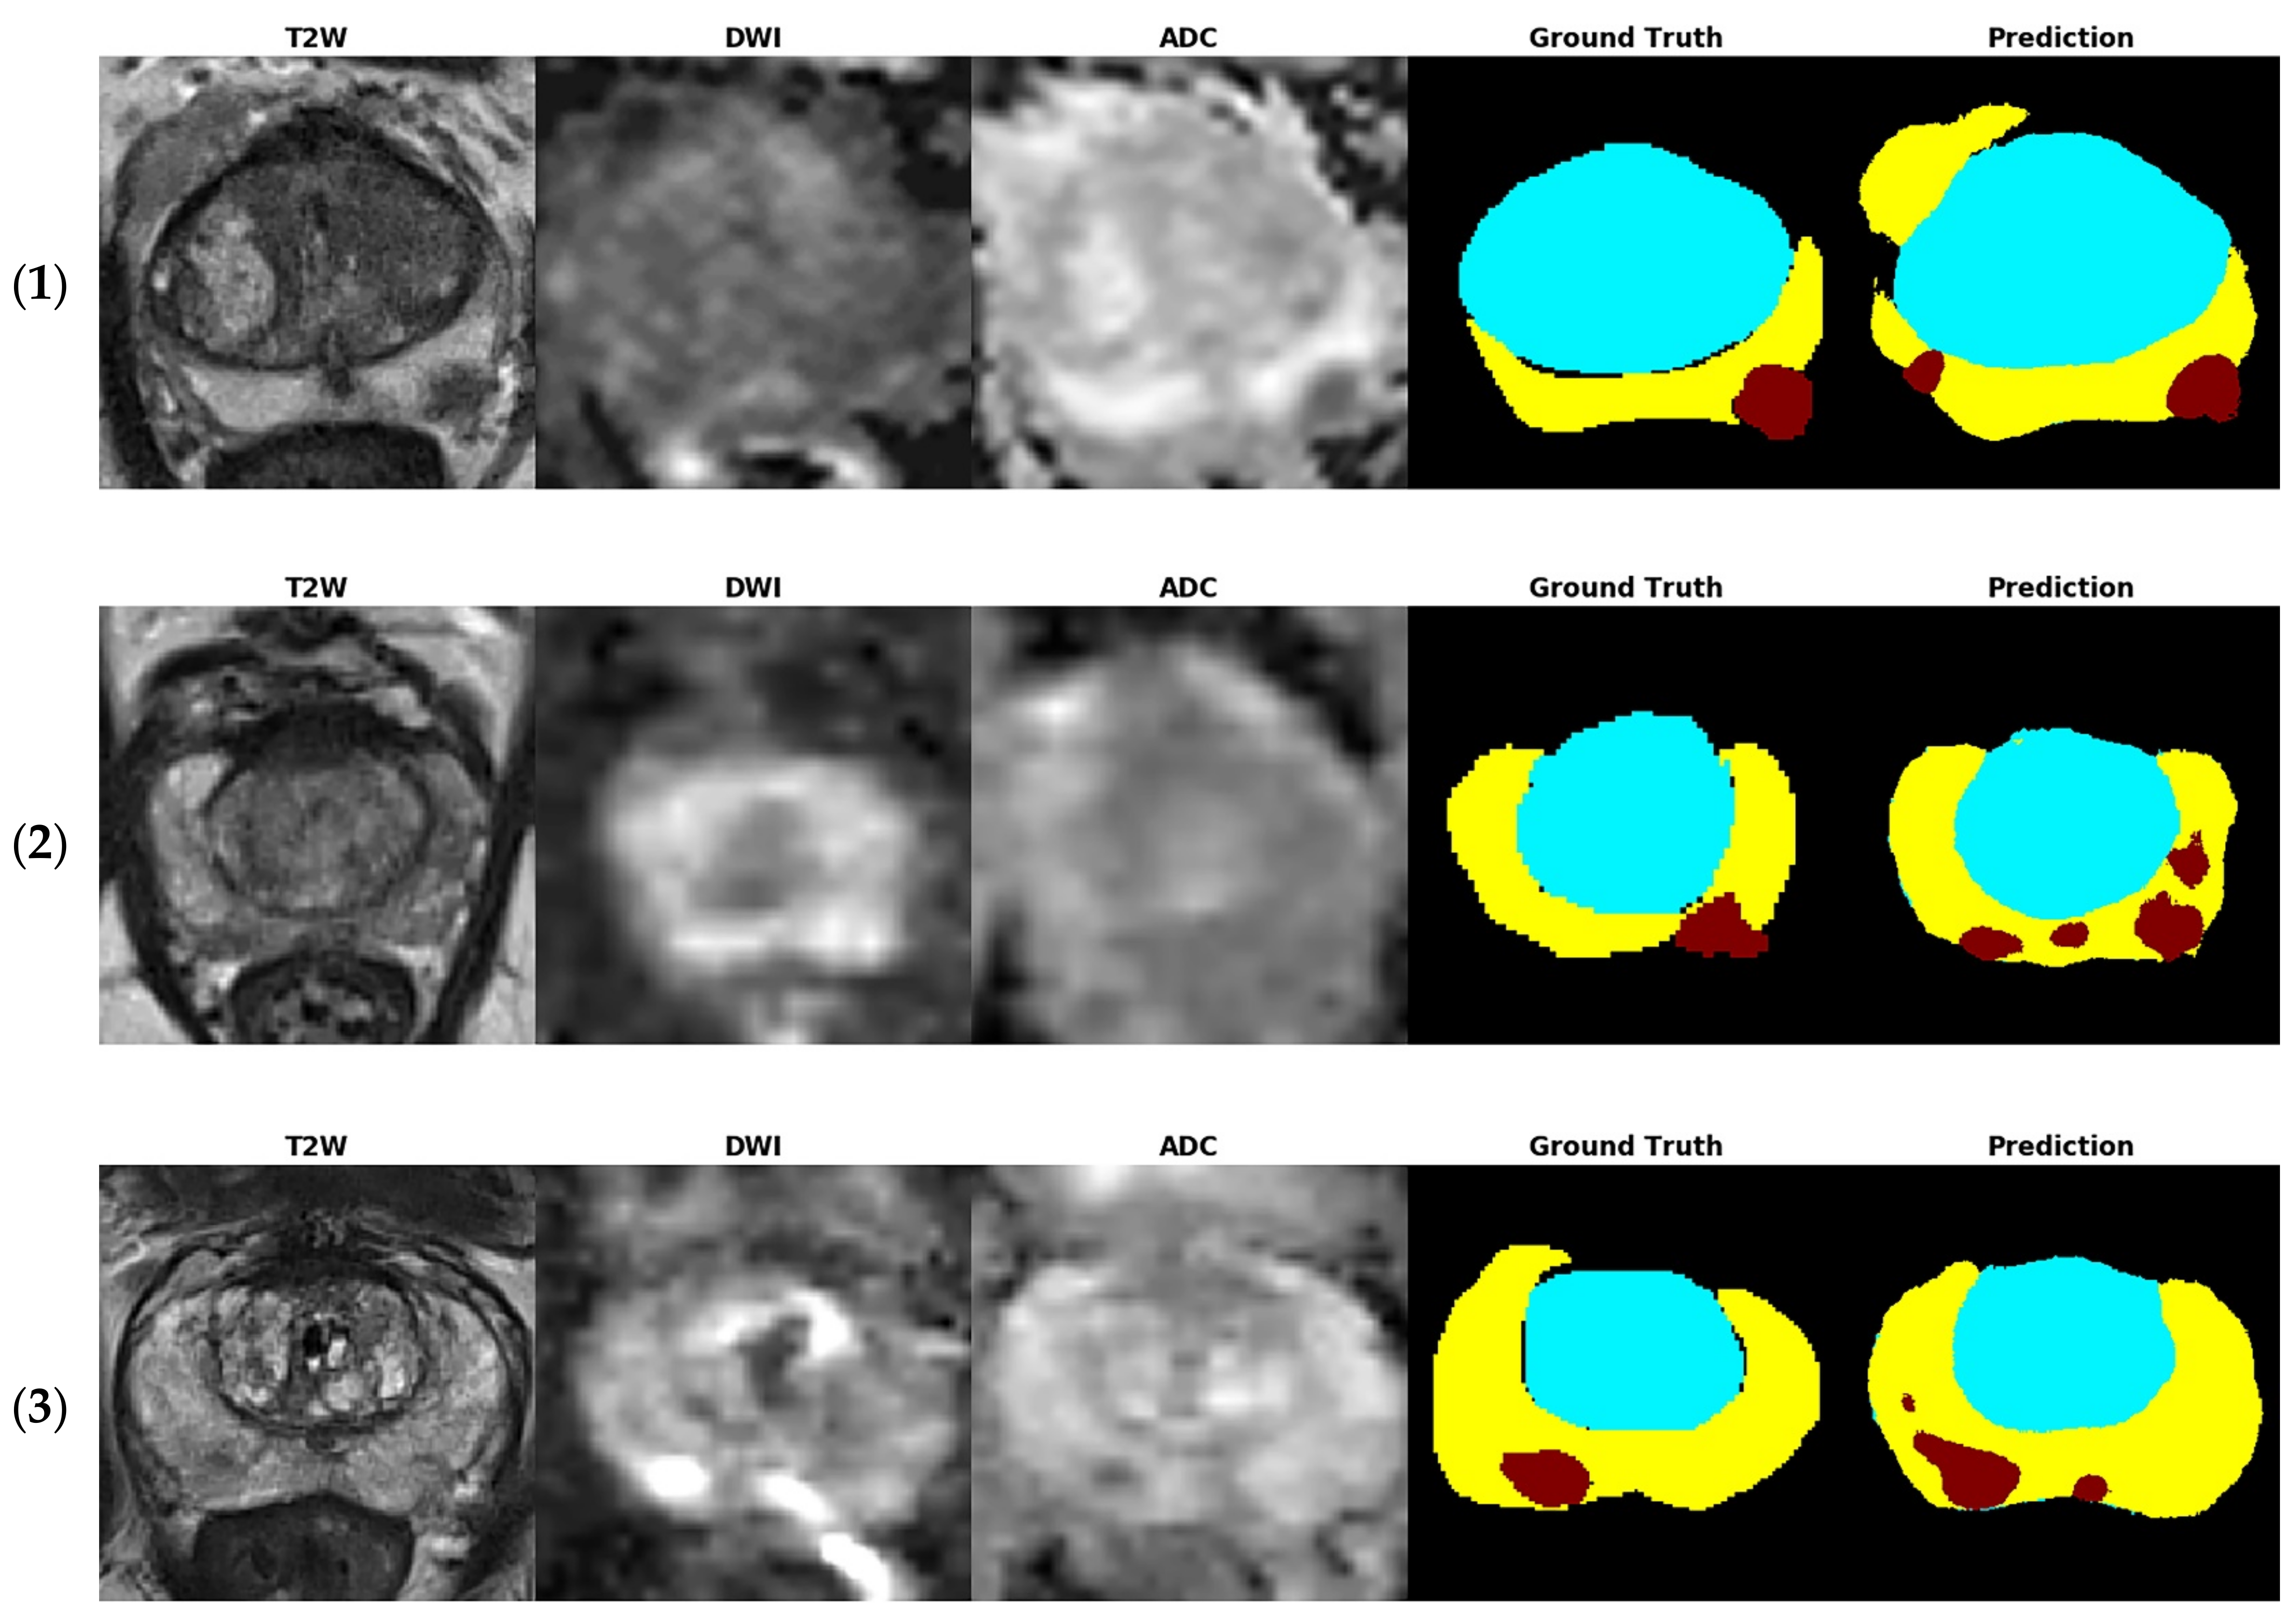

Figure 4 shows several examples of test images in the T2W image + DWI + ADC image model. The ground truth images of segmentation and the corresponding prediction results are illustrated in the aforementioned figure. The TZ in the prediction image was generally similar to that in the ground truth image. The PZ region generally was in the correct location, with considerable discordance at the boundary between true labeled image and predict image. The true PCa regions were observed in the prediction images, and FP predictions were common, especially in the PZ (9% to 12%), as indicated in the confusion matrix in Figure 3. By inspecting the original MRI images, we speculate that these FP regions were mainly formed due to the inflammation process. Moreover, in contrast to the label images, the PCa regions were usually underestimated in the prediction images, which may explain the high number of FNs of PCa in the PZ (23–39%).

Figure 4. Test images of five patients (15) in the T2W image + DWI + ADC image model. The tumor location was provided from dataset. The ground truth images of segmentation and the corresponding prediction results are illustrated (blue region: TZ, yellow region: PZ, and red region: PCa).